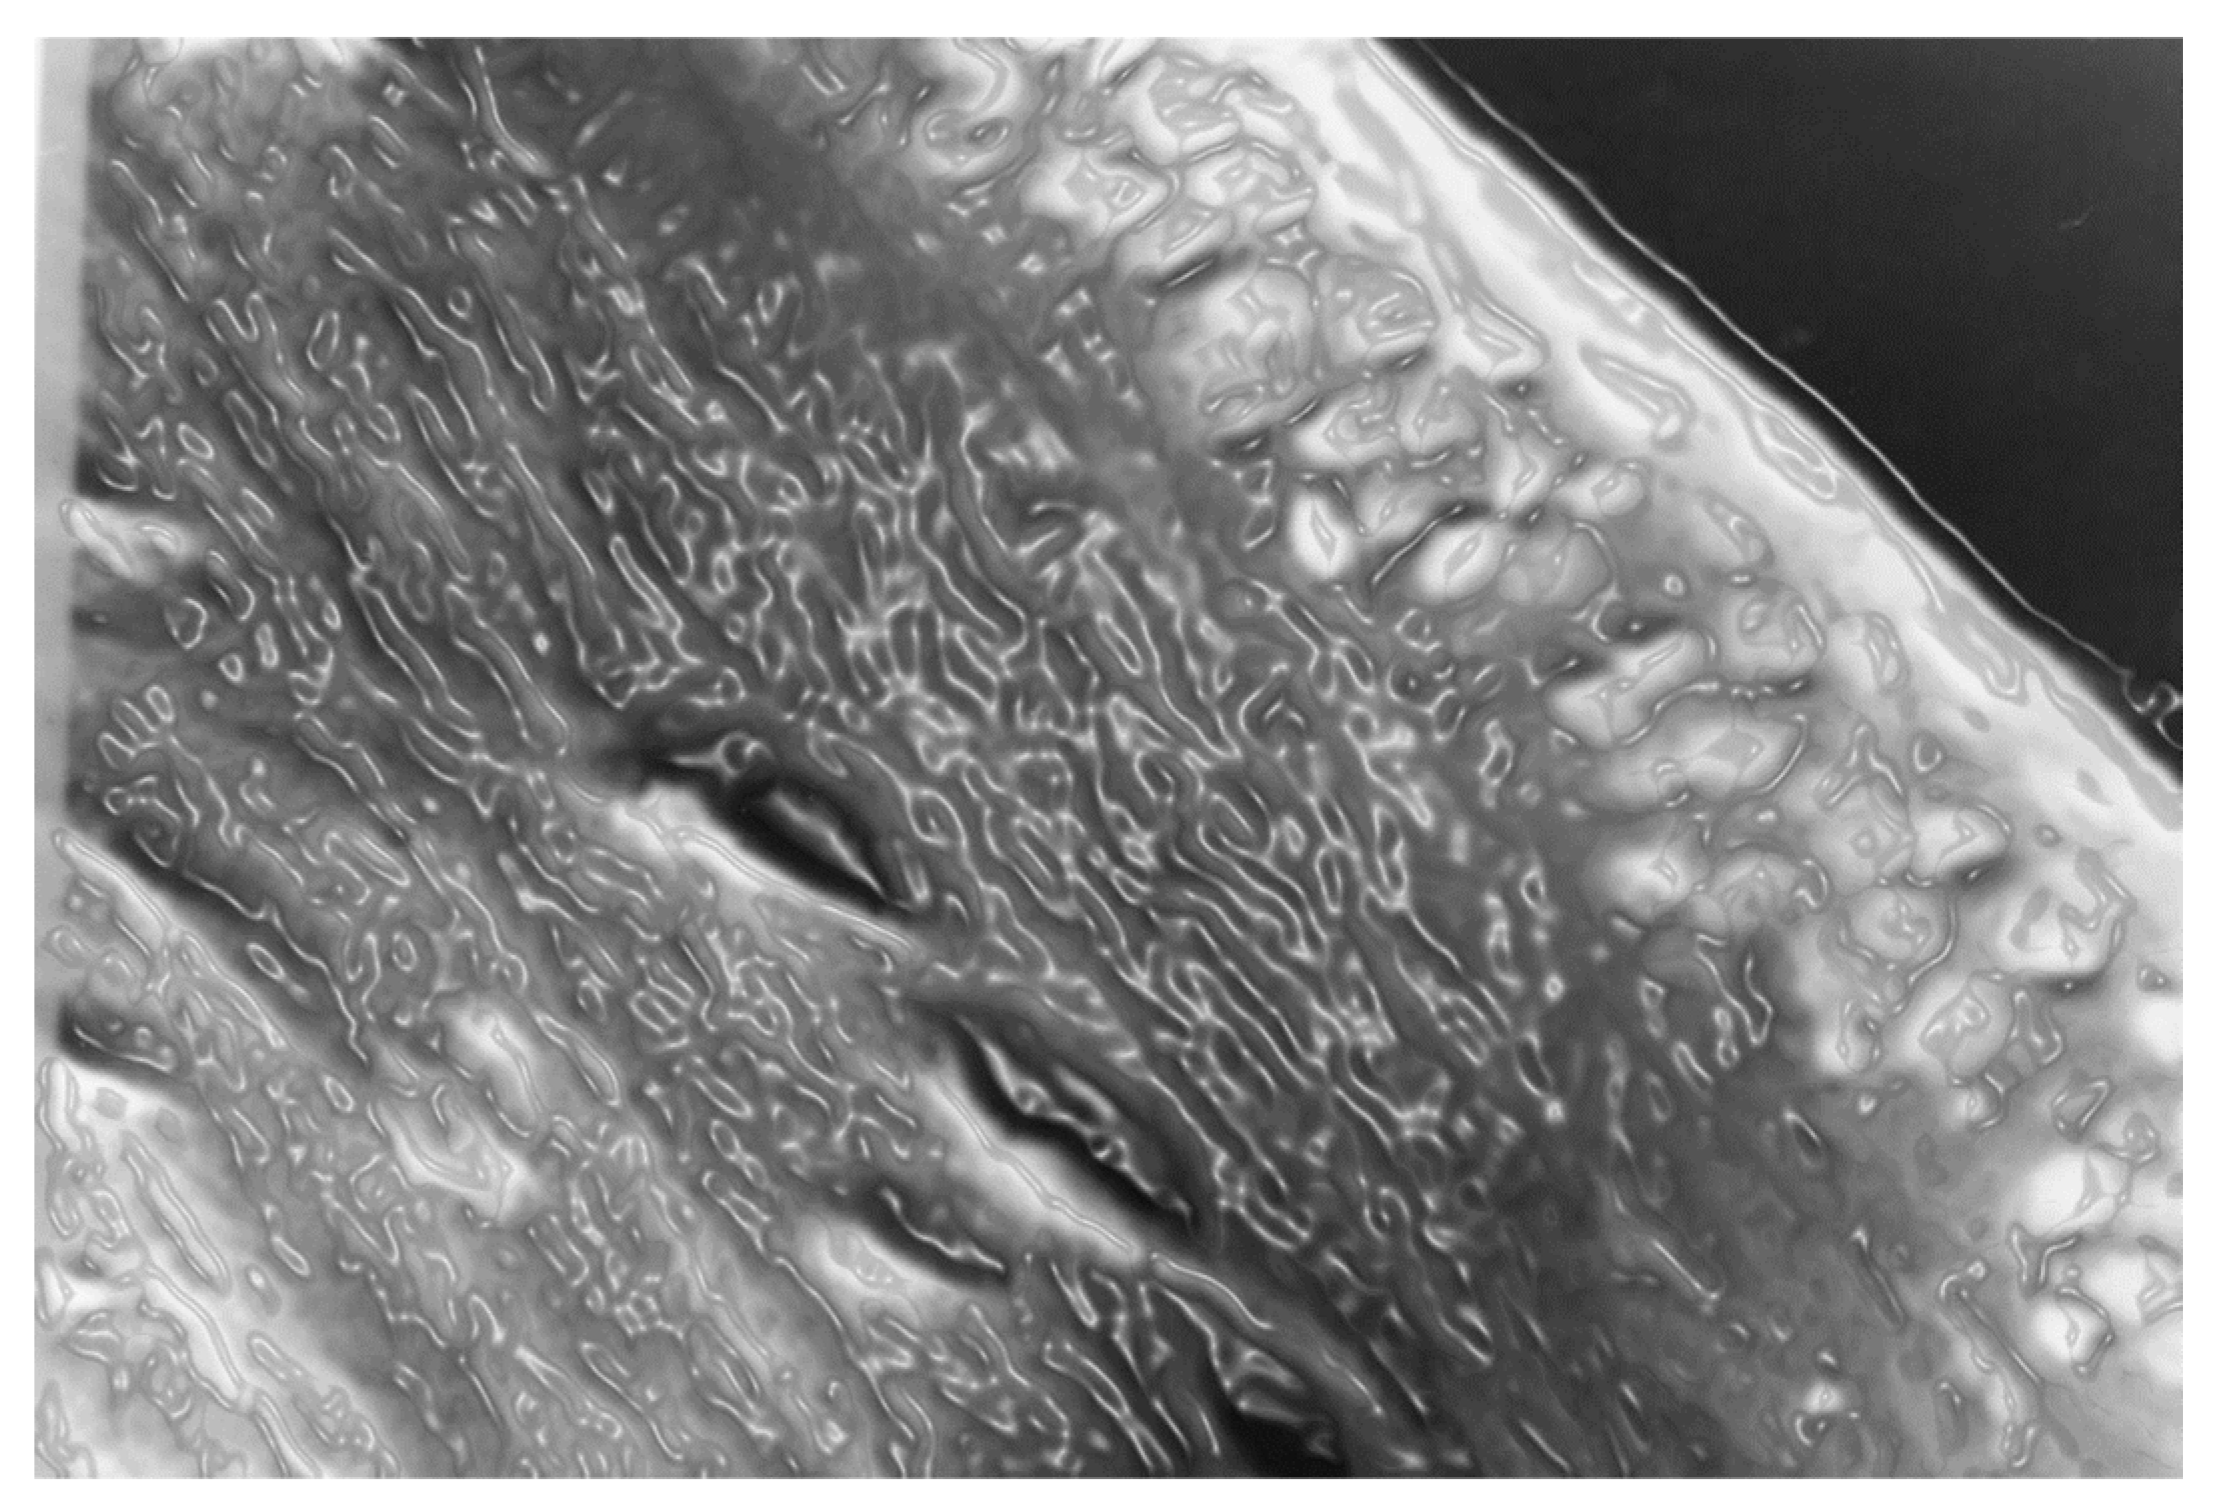

Figure 13. The photomicrograph of Figure 12, with a computer-assisted effect to give an idea of how the tissues would look in the presence of water. Let us remember that they are normally dehydrated during staining on purpose to study the histological sections under a microscope examination making visible intracellular structures that otherwise appear invisible under a light microscope.